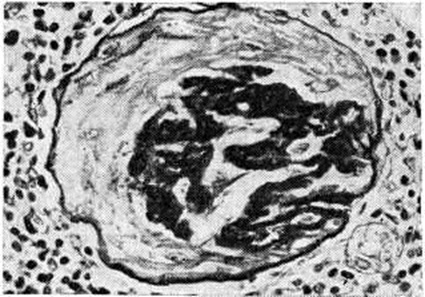

Доброкачественная форма характеризуется артериолосклерозом (рисунок 1), нередко в сочетании с атеросклерозом почечной артерии и её крупных ветвей, атрофическими изменениями групп нефронов с вторичным гиалинозом клубочков (рисунок 2), увеличением соединительнотканной стромы, гиалинозом сосочков пирамид. Макроскопически поверхность почек мелкозернистая, а при сочетании с атеросклерозом — крупнобугристая. По мере нарастания артериолосклеротических изменений, сочетающих плазморрагию (смотри полный свод знаний) и гиалиноз (смотри полный свод знаний), и выключения новых групп нефронов развивается почечная недостаточность (смотри полный свод знаний). Злокачественной форме свойственны фибриноидный некроз артериол (артериолонекроз) и капиллярных петель клубочков (рисунок 3, а), отёк стромы, кровоизлияния, белковая дистрофия эпителия канальцев. Очень быстро в ответ на некротические изменения развивается склероз почек (рисунок 3, б). Подобные изменения могут возникать и при эклампсии (злокачественный постэкламитический Нефросклероз).